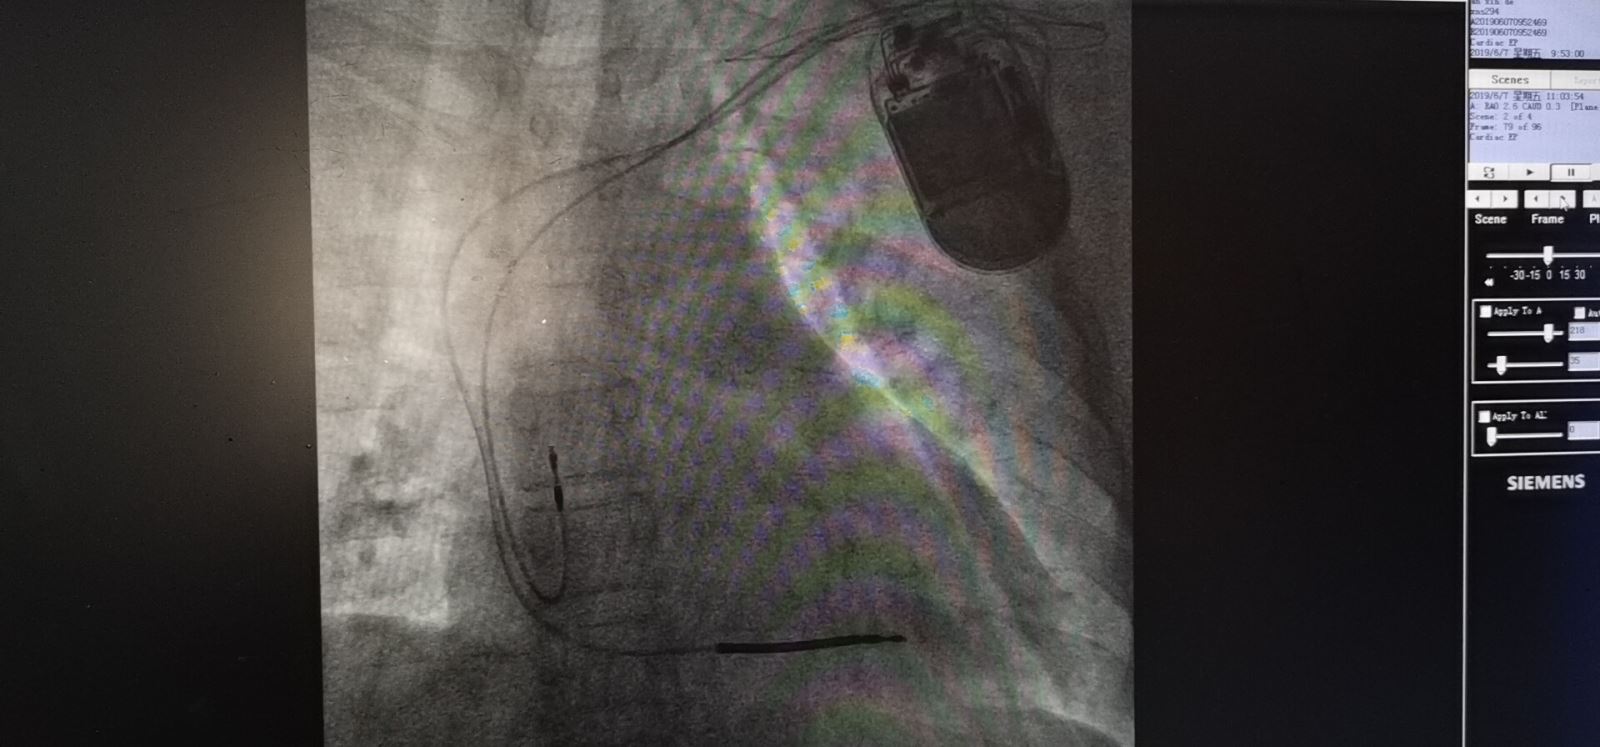

近日,我院心血管内三科成功完成了市医院首例植入型心律转复除颤器(ICD)植入术,此项技术的开展标志着我院恶性室性心律失常的治疗再上一个新台阶。

接受这例双腔ICD植入手术的是一位40岁的男性患者,既往反复晕厥2次伴摔伤,日前再次病发入住我院心血管内三科。住院期间再发室性心动过速伴血流动力学障碍,虽经药物治疗后恢复了窦性心律,但恶性心律失常已经严重危及到了患者的生命安全。

心内三科杜建军主任组织全科人员进行了病情会诊及讨论,经慎重考虑,确定了为患者安装ICD的治疗方案。经患者及家属同意后,医生成功为患者实施了双腔ICD植入术,避免了恶性事件的发生,挽救了患者的生命,现患者已康复出院。